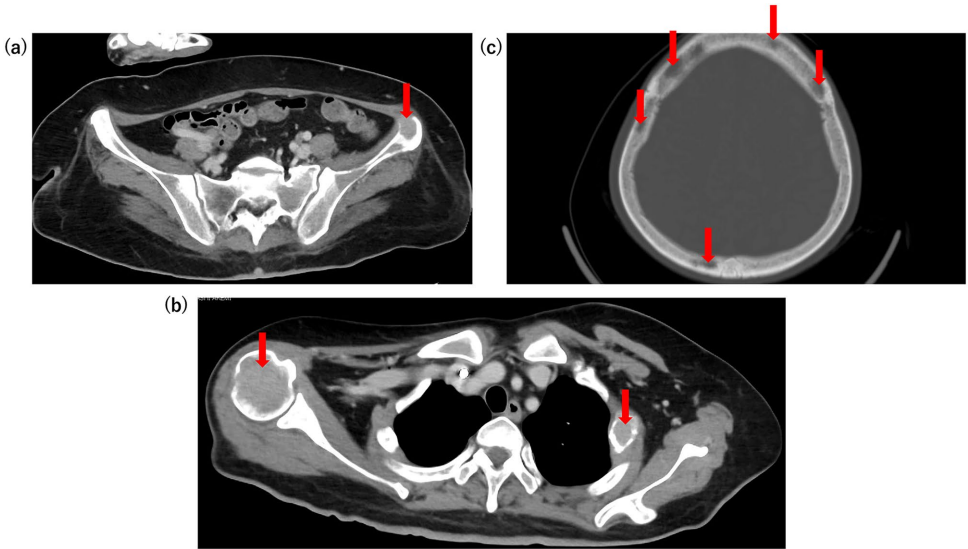

【影像学发现】CT扫描揭示多发性溶骨性病变,累及右肱骨、左第二肋骨、颅骨和骨盆。这些病变被认为是高钙血症的罪魁祸首。